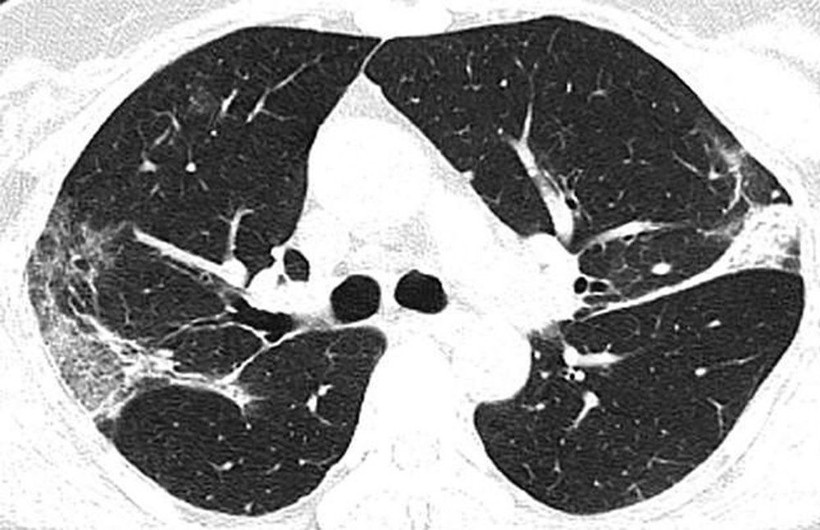

Filmlerde akciğerdeki hava boşluklarının çoğunluğunun virüs nedeniyle dolduğu görülüyor. Uzmanlar, taramalarda görülen beyaz lekelerin SARS ve MERS’te de mevcut olduğunu belirtti. Kuzey Amerika Radyoloji Derneği (RSNA), yeni tip corona virüsün (Covid-19) ortaya çıktığı Çin’in Wuhan kentindeki salgının kaynağı olduğu düşünülen deniz ürünleri pazarında çalışan ve 44 yaşında virüs nedeniyle hayatını kaybeden bir adamın röntgen filmlerini kamuoyuyla paylaştı.

Filmlerde corona virüsün akciğerleri nasıl tahrip ettiği net bir şekilde görülüyor. X-ray ışını taramalarında corona virüsün etkileği yerler beyaz olarak görülüyor. Uzmanlar, hastada virüsün akciğerlerdeki hava keseciklerini kısmen doldurduğunu ve akciğer nodüllerine sebep olduğunu belirtti. Diğer taraftan aynı tip anormalliklerin SARS (Şiddetli Akut Solunum Sendromu) ve MERS (Ortadoğu Solunum Sendromu) vakalarında da görüldüğünü söylediler.